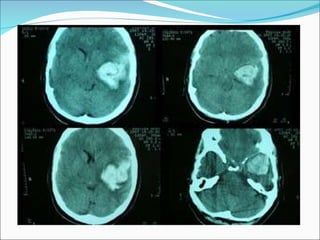

HEMATOMA SUBDURAL AGUDO Entre el 37 and 80%  HSA  ingresa con  Glasgow < 8. Mortalidad 57 and 68% con Qx. Ruptura de venas comunicantes entre la corteza cerebral y la duramadre. Laceraciones cerebrales o lesiones de arterias corticales.  Se localiza con más frecuencia en regiones de contragolpe.  TAC como lesiones hiperdensas  con forma de semiluna y bordes menos nítidos que el anterior .

CONTUSION HEMORRAGICA Es la más frecuente en un TCE. Areas subyacentes a zonas óseas prominentes. Rara vez se lesionan las regiones occipitales y el cerebelo.

CONTUSIONES HEMORRAGICAS

HEMATOMA INTRAPARENQUIMATOSO  Área hiperdensa, intracerebral Límites bien definidos Volumen superior a los 25 cm3.